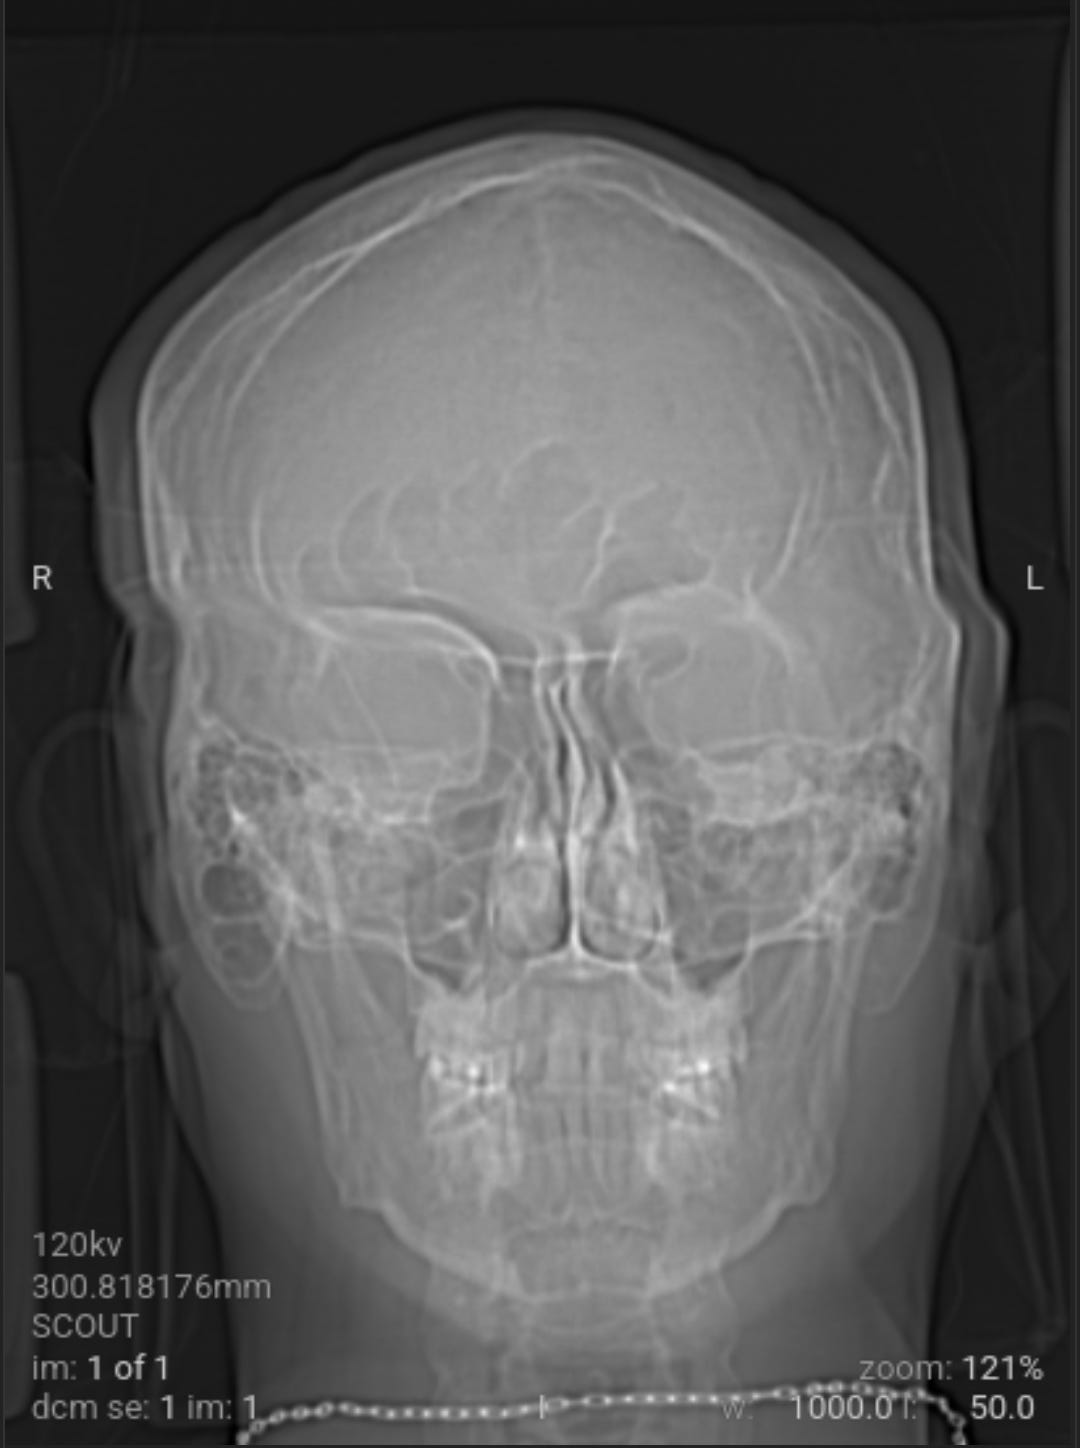

As a followup to eliminate all possible and probably causes of the weaponized audio-video-communications and pathogen nanotechnology. Got blood work and CAT scan done. Results came back good.

As a followup to eliminate all possible and probably causes of the weaponized audio-video-communications CNT and pathogen nanotechnology WPT, I got blood work and CAT scan done yesterday. All came back good with the exception of a low Red Blood Cell RBC count due to my cleansing diet on vegetables and plant based proteins that needs more iron in it with vitamin C, I already dose with vitamin B12 (preference is methylcobalamine). The medical staff could not determine what the unknown material removed from my body was from the salt baths or the material that moved around and itches at times on the left side of my head.

The void spaces on left side are what I suspect to be where the nanotechnology circuitry was removed by magnetic vortex skyrmion unit, chelators, salt water baths, no yeast diet and no added sugar diet. Note the scans do not show any nanotechnology based synthetic biology parasites. This is why the samples pulled from my body were classified as unknown by the western medical staff not trained in the nanotechnology and synthetic biology knowledge domain, a huge gap in Western medicine.